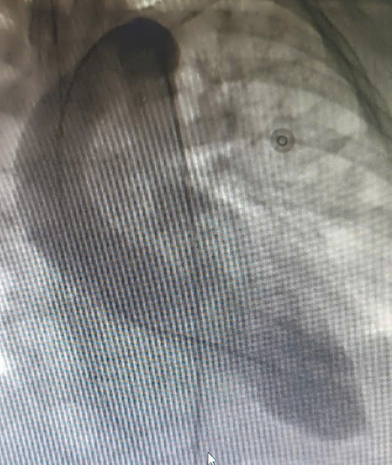

| C: Hình giỏ Takotsubo với đáy tròn cổ hẹp tại Nhật Bản - Ảnh BVCC |

Takotsubo là hình ảnh chiếc bẫy bạch tuộc trong tiếng Nhật. Hội chứng Takotsubo, một dạng bệnh cơ tim cấp, xảy ra do cơ thể phản ứng với căng thẳng cực độ bằng cách giải phóng quá mức catecholamine. Sự gia tăng đột ngột của các hormone này làm co thắt vi mạch và suy giảm chức năng tim, gây ra các triệu chứng giống như nhồi máu cơ tim nhưng không do tắc nghẽn động mạch vành.